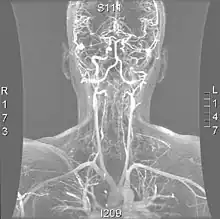

- Magnetic resonance imaging (MRI)

Magnetic resonance imaging has the ability to quantify the plaque anatomy and composition. This allows physicians to determine certain characteristics of the plaque such as how likely it is to break away from the wall and become an embolus. MRI does not use ionizing radiation, so the number of times that it is used on a single person is not a concern; however since it uses strong magnetic fields those who have metal implants cannot use this technique.[1][2]